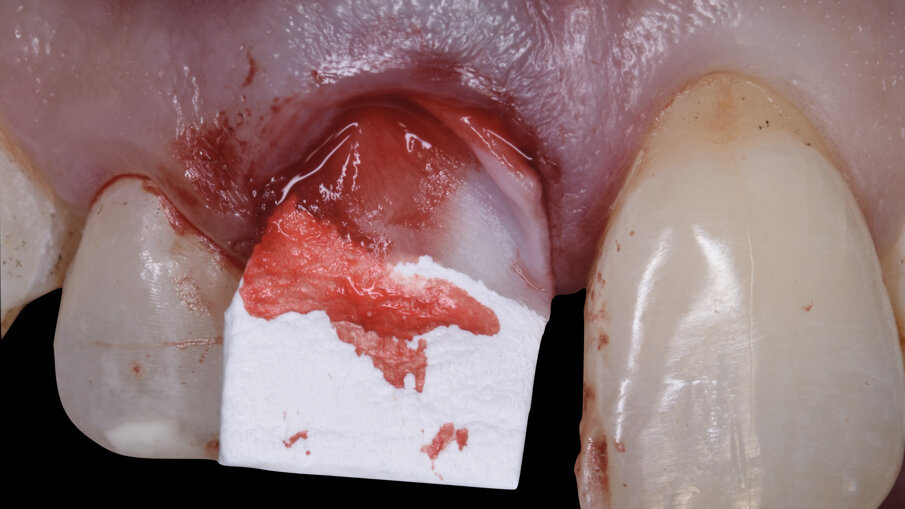

È stata quindi eseguita un’incisione vestibolare intrasulculare del sito senza toccare le papille, facendo scorrere la lama sul piano osseo crestale, e nella porzione più apicale dove era presente la discontinuità della corticale si è spostato la lama mesiale e distale e ancora apicale fino a ritrovare il piano osseo secondo le indicazioni della CBCT; è stato possibile così inserire una membrana in collagene suina Geistlich Bio-Gide (Geistlich Pharma AG, Wolhusen, Switzerland) opportunamente sagomata in modo che avesse un appoggio sui piani ossei (Fig. 4); all’interno dell’alveolo è stato posizionato Geistlich Bio-Oss Collagen (Geistlich Pharma AG, Wolhusen, Switzerland), osso bovino deproteinizzato con un 10% di collagene suino addizionale, materiale osteoconduttivo che oltre a essere mantenitore di spazio e scaffold per la rigenerazione ossea, funge anche da sostegno per il tessuto molle soprastante (Fig. 5). Si è quindi proceduto dopo anestesia palatale a un prelievo tramite bisturi circolare di un punch epitelio connettivale di forma tondeggiante e misure simili all’alveolo dell’1.1 da sigillare; dopo la disepitelizzazione dei margini dell’alveolo si è proceduto alla sutura del punch al di sopra del sostituto osseo con suture Vicril 6-0 (Johnson & Johnson Medical Spa, Pomezia RM, Italia) con punti staccati alle quattro estremità e sutura a materassaio esterno incrociato compressiva (Fig. 6). In questa fase la paziente è stata riabilitata con un maryland bridge in composito cementato adesivamente.

La tecnica di Ridge Augmentation permette, come nel caso clinico descritto, una rigenerazione ossea guidata all’interno del sito estrattivo contestuale all’estrazione in una situazione anatomica di lieve o medio difetto osseo. Il posizionamento di una membrana riassorbibile in collagene suino vestibolare al difetto osseo e la gestione dell’alveolo estrattivo con un biomateriale osteoconduttivo ottimizza la guarigione del sito estrattivo limitando l’entità delle procedure rigenerative al momento del posizionamento successivo dell’impianto16, 19, 20.

La procedura di Ridge Augmentation si completa e trova un miglior risultato clinico quando è associata anche a una tecnica di Socket Seal21: la chiusura dell’alveolo estrattivo con un innesto epitelio connettivale permette di compensare in parte il riassorbimento verticale dei tessuti molli e determina un aumento del volume dei tessuti alla base della futura papilla, permettendone la sua corretta riformazione in base alle indicazioni espresse da Tarnow e Roccuzzo8, 22.